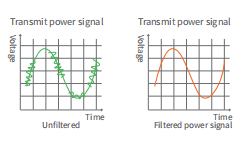

The electromagnetic guard processing of

whole system is to prevent the ultrasonic signal from electromagnetic interference

during the transmission process, to ensure the stability of the signal trans

mission, so as to obtain a clearer image.